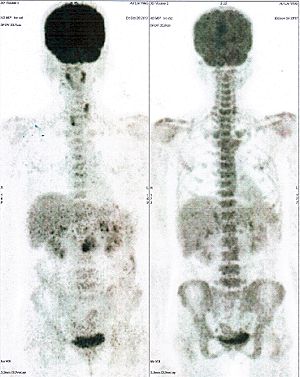

CASE NO: 2 (HEPATOCELLULAR CARCINOMA)

A 40+ man with hepatocellular carcinoma, an incurable cancer. After 2 treatment, the activity of the hepatocellular carcinoma is less.

CASE NO: 2 (HEPATOCELLULAR CARCINOMA) - After a few more treatments

After another few treatment, the activity of the hepatocellular carcinoma is much less. The patient never came back for further treatment, but this case, and case no: 1, shows that incurable hepatocellular carcinoma, often seen in hepatitis B and C patients, can be cured.